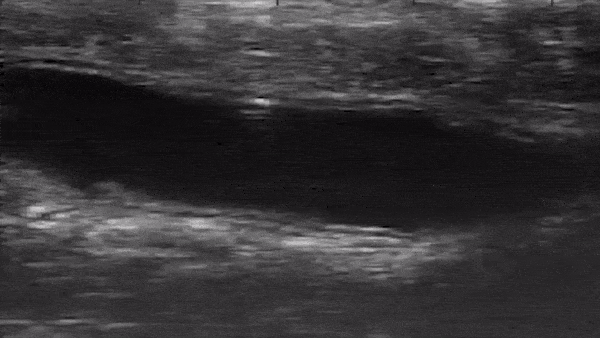

연구진이 공개한 영상은 초음파 장비를 통해 로봇이 이동을 실시간으로 확인한 것이다. 또 폴리머와 금속으로 저렴하게 만들어진 이 로봇은 독성이 없고 생체에 적합한 것으로 확인됐다.